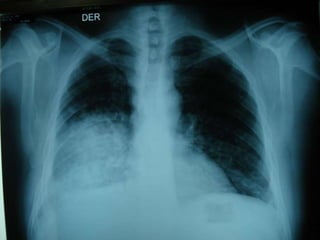

NEGATIVO Edema pulmonar

Infiltrados alveolares

con tendencia a

distribución periférica,

dejando

más oscuras zonas centrales

NEUMONÍA EOSINÓFILA CRÓNICA

Es el negativo de EAP

o el

signo de las alas de mariposa invertido

Signo de ala de mariposa (edema

pulmonar)